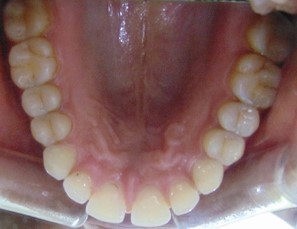

Divya Patil, 28Y, Duration - 6Months

Before

After

Image 1